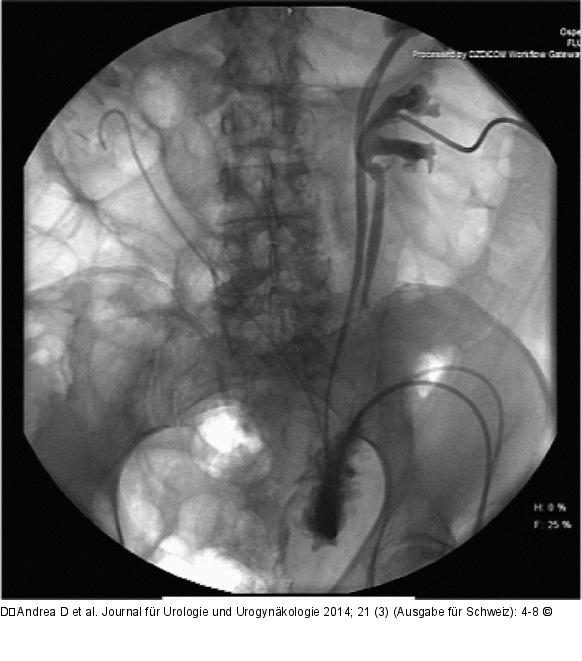

Abbildung 1: Urinleckage Urinleckage eines Kolon-Conduits mit Wallace-Platte: An der Anastomosenstelle ist ein Austritt von KM sichtbar. Links handelt es sich um ein doppeltes Nierensystem mit Ureter fissus. |

Urinleckage eines Kolon-Conduits mit Wallace-Platte: An der Anastomosenstelle ist ein Austritt von KM sichtbar. Links handelt es sich um ein doppeltes Nierensystem mit Ureter fissus. |